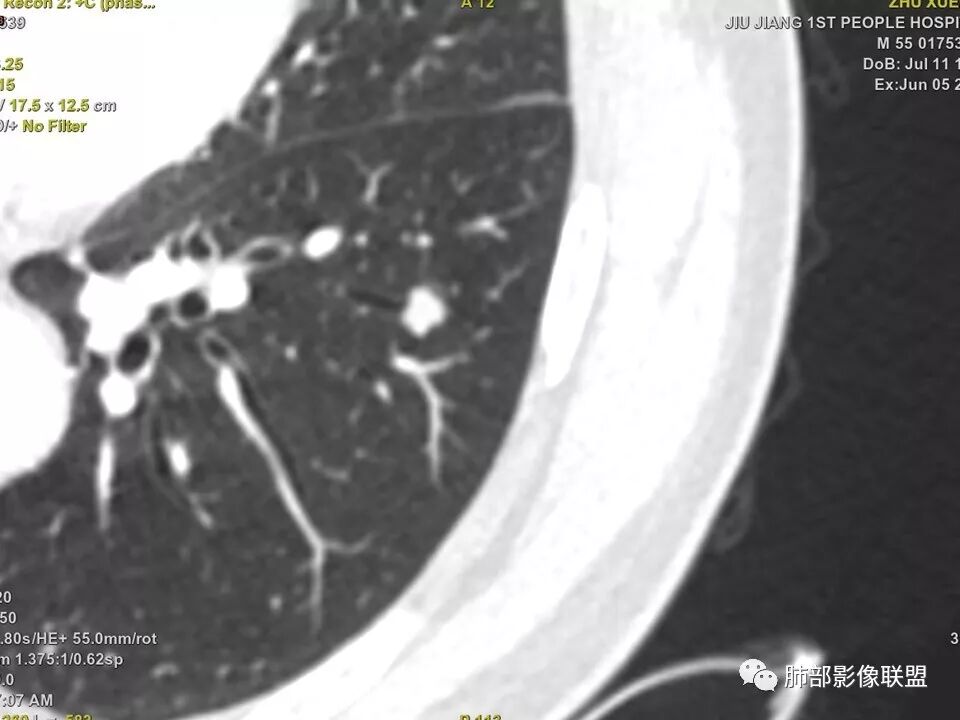

中年男性,左肺下叶不规则实性结节,有分叶及棘状凸起,支气管截断,轻度不均匀强化,考虑鳞癌,鉴别炎性肉芽肿。

实性结节,深分叶,支气管截断,考虑腺癌。只是强化有点低。鉴别:肉芽肿病变。

左肺下叶前内基底段结节 深分叶和脐凹 表面部分膨隆 部分收缩 支气管截断 轻度强化 中央有坏死 考虑鳞癌 鉴别炎性结节

中年男性,支气管门口截断、邻近支气管未见管壁增厚,分叶明显,边缘彭隆,内见小坏死灶,周围未见GGO,考虑周围性鳞癌,鉴别炎性肉芽肿。

病灶多结节融合,有分叶,也支气管截断,有细小血管连接,考虑恶性结节,周围型肺癌。

中年男性,左肺下叶不规则实性结节,有桑葚感和分叶,支气管截断,不均匀强化,有坏死,考虑鳞癌可能性大。

左下肺前内基底段结节灶,边缘分叶,相应支气管截断,增强后轻度强化,中央可见坏死。考虑麟癌。

典型CT特征包括:(1)圆形或椭圆形边界清楚的病灶。(2)大小1~4cm,有轻微分叶改变。(3)较均匀的软组织影,多伴有钙化。(4)无毛刺,卫星灶及肺门或纵隔淋巴结肿大。(5)CT增强扫描无强化或轻度强化,其强化可能与软骨瘤间质中的薄壁血管或周围慢性炎症反应有关。